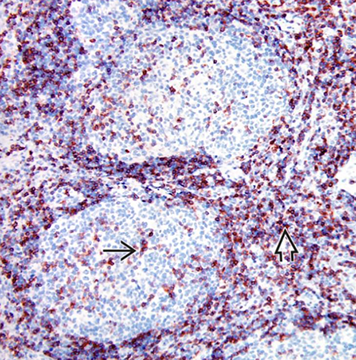

Reactive follicular hyperplasia (arrow to focal paracortical hyperplasia) [2]

CD3 in reactive follicles. Immunohistochemical stain for the pan T-cell marker CD3 highlights scattered small lymphocytes within germinal centers (solid black line). Many more CD3(+) lymphocytes are noted in the interfollicular region .(open black line) [2]

Immunohistochemical stain for Bcl-6 highlights centrocytes and centroblasts in the reactive germinal centers (open blue arrow) Mantle zone lymphocytes (straight black arrow) are negative; rare or scattered interfollicular lymphocytes (curved black arrow) are positive for Bcl-6. - Ki67 looks similar

Hyperplastic lymphoid follicle. Germinal center with sharply demarcated mantle zone (solid blue arrow). Dark zone of GC with starry-sky pattern (open blue arrow) and light zone (open black arrow) with small centrocyte predominance [2]

High magnification of GC with centroblasts (solid blue line) mixed with histiocytes with clear cytoplasm with nuclear fragments (open black line) and frequent mitoses (curved black line)